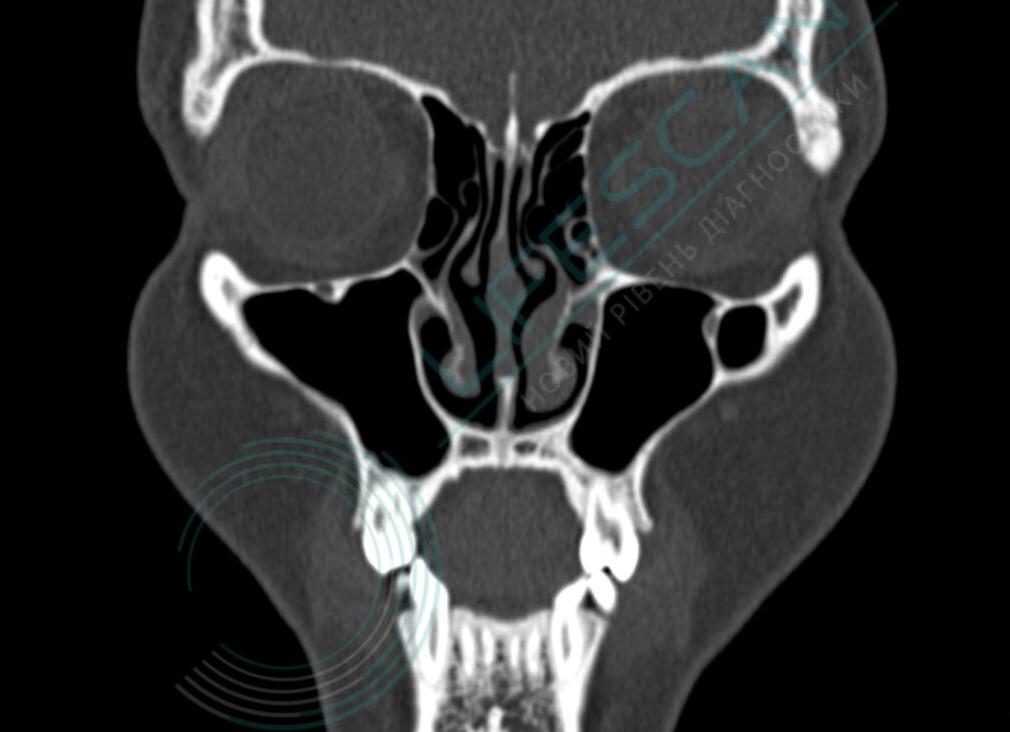

Компьютерная томография шеи

Компьютерное сканирование шеи и головы, гортани назначается ЛОР-врачом, гастроэнтерологом, онкологом. Исследование показывает строение позвонков, состояние сосудов, соседних органов.

По качеству томография значительно превосходит рентгенографию, хотя в основе лежит рентгеновское излучение. Изготовление серии срезов исследуемой области через несколько миллиметров, программное создание пространственной модели – особенности увеличивают чувствительность, специфичность исследования.